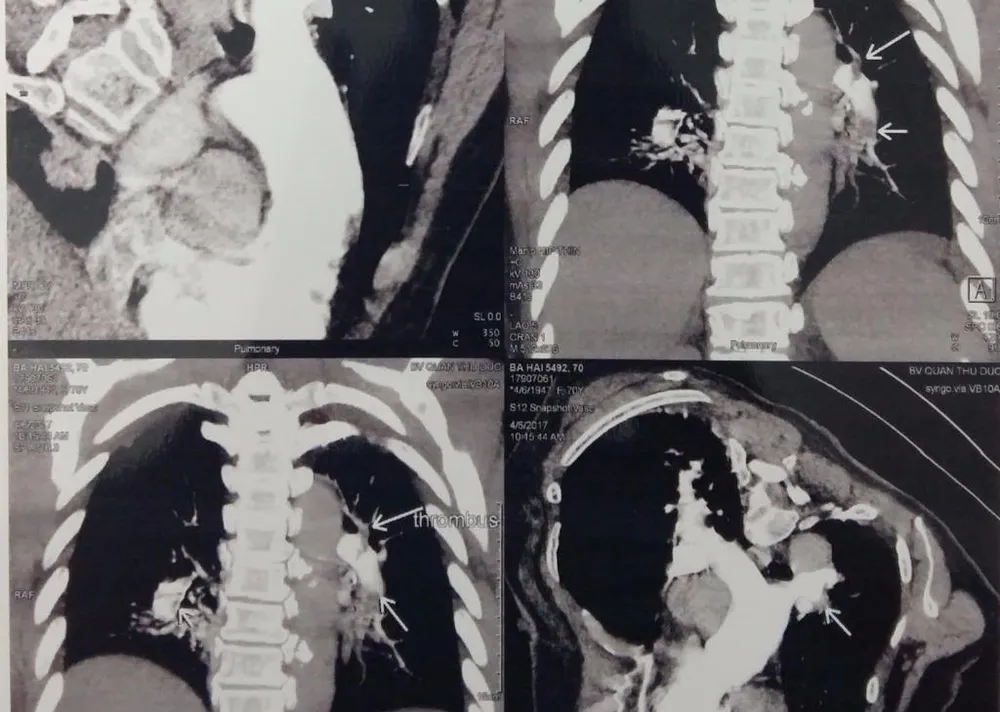

Kết quả ghi nhận có nhiều huyết khối trải dài từ các nhánh phải và trái của động mạch phổi lên các nhánh phân thùy phổi. Các bác sĩ kết luận bệnh nhân ngưng tim, ngưng thở là do thuyên tắc phổi cấp gây ra.

Hình ảnh huyết khối trong các nhánh động mạch phổi của bệnh nhân

Hình ảnh huyết khối trong các nhánh động mạch phổi của bệnh nhân BH. Ảnh: XUÂN CHI